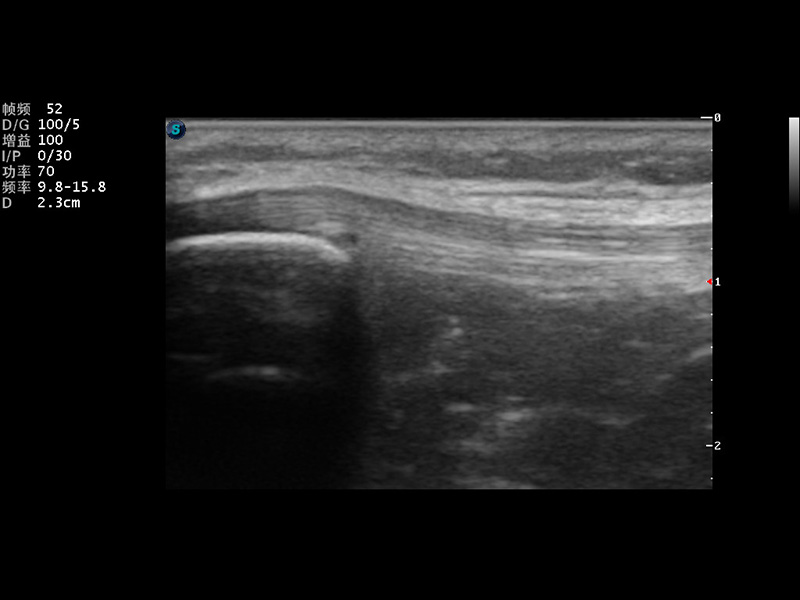

S9便携式彩色多普勒超声诊断仪是玖鼎集团研发的高端便携彩超设备,外观设计新颖、产品性能卓越。S9在便携超声领域采用了突破传统的触摸屏交互设计,并以先进的软件硬件技术和设计理念,为您带来清晰的图像质量、稳定的工作性能和便捷的操作体验。

μ-Scan微米成像

实时宽景成像